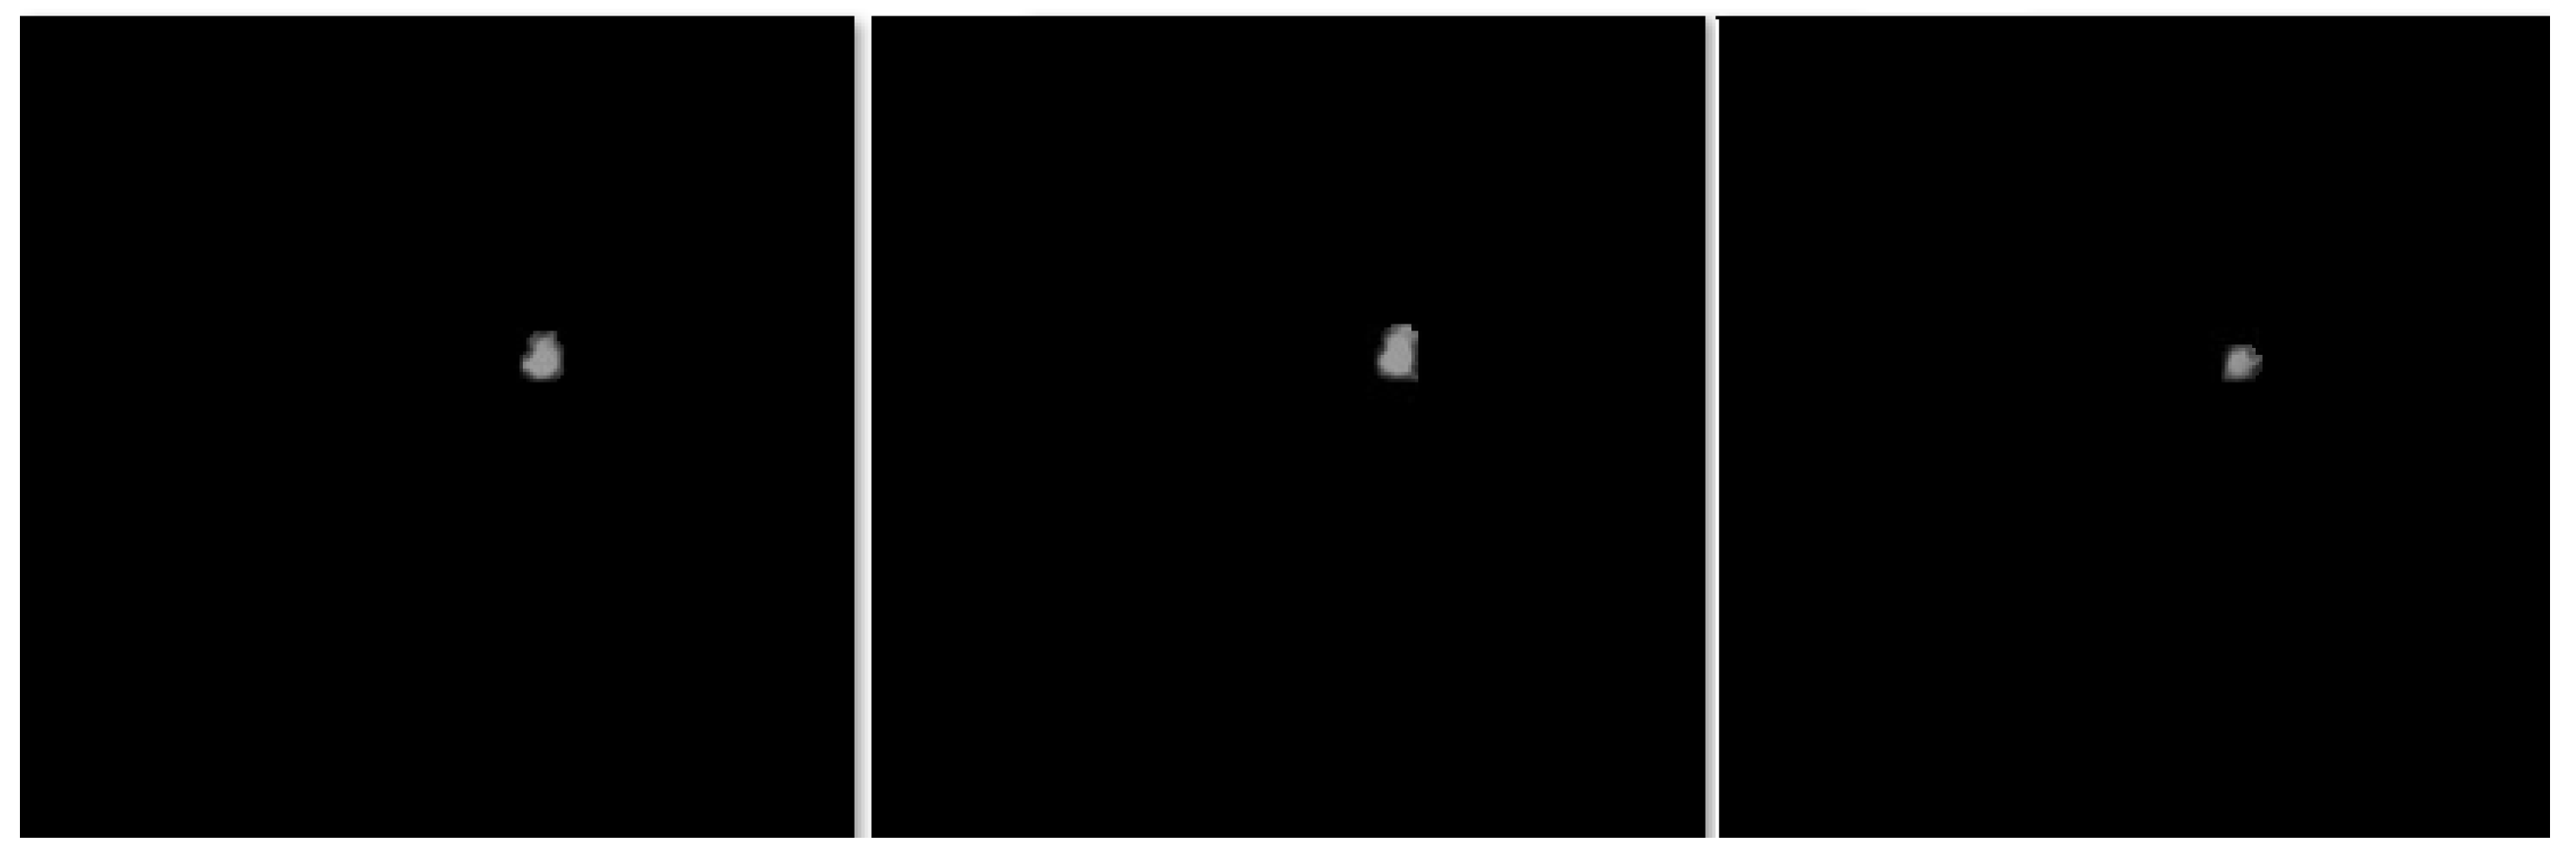

In this section, the segmentation results of the RW-ensemble are visualized for distinct types of nodules. The results for three different types of nodules from the LCT-D dataset are demonstrated: solid nodules, juxta-vascular, and pleural nodules. To improve clarity, each case is visualized through CT slices and the corresponding RW-ensemble segmented outputs, organized by nodule type and patient ID. Figure 6 and Figure 7 represent the solid nodule and its respective RW-E segmented images in grey-scale for patient R_0108. The juxta-vascular nodules of patient R_0052 are shown in Figure 8, and the corresponding RW-E segmented output images are illustrated in Figure 9. Juxta-pleural nodules, which are challenging due to their attachment to the lung wall, are illustrated in Figure 10 and Figure 11 for patient QIN_LSC_0064.

Figure 7. RW-ensemble segmentation output of the solid nodule in grey-scale.

Figure 9. RW-ensemble segmentation output of juxta-vascular nodules in grey-scale.